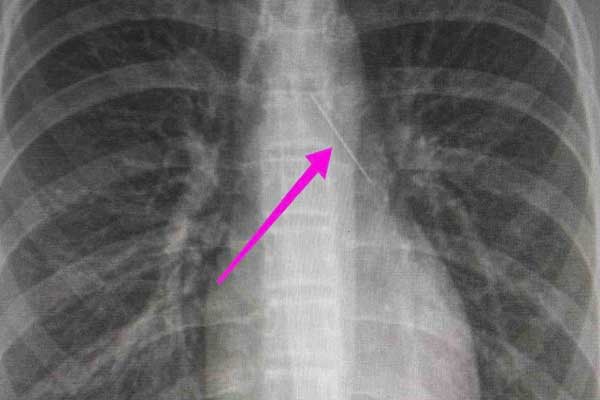

Από την απεικονιστική διερεύνηση που πραγματοποιήθηκε με ακτινογραφία θώρακος αρχικά και ακολούθως με αξονική τομογραφία θώρακος, διαπιστώθηκε «η ύπαρξη αιχμηρού μεταλλικού ξένου σώματος στην αναπνευστική οδό (αριστερός κύριος βρόγχος) και όχι στην πεπτική οδό».

Κατά την βρογχοσκόπηση διαπιστώθηκε η μετακίνηση και ενσφήνωση του ξένου σώματος στον δεξιό κύριο βρόγχο. Μετά από εργώδεις προσπάθειες ολοκληρώθηκε με επιτυχία η αφαίρεση του.